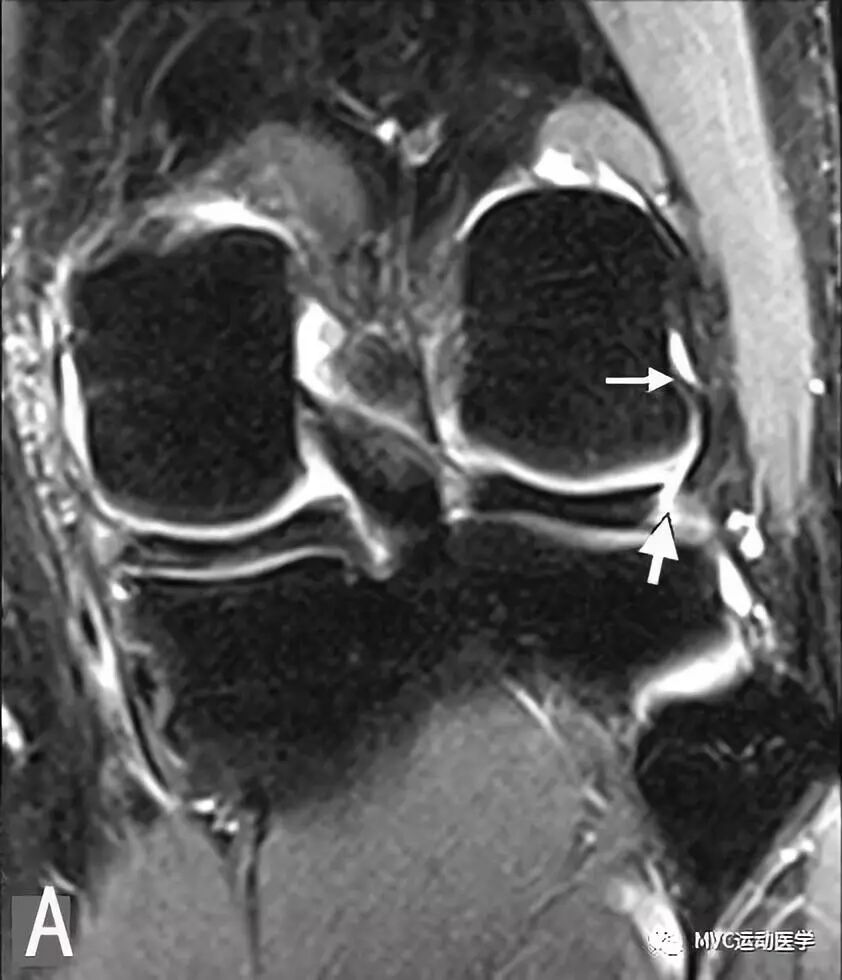

A:冠状位MRI显示腘肌腱裂孔(白色宽箭头)与腘肌腱(白色细箭头);

B:冠状位MRI显示腘肌腱(白色箭头)穿过腘肌腱裂孔;